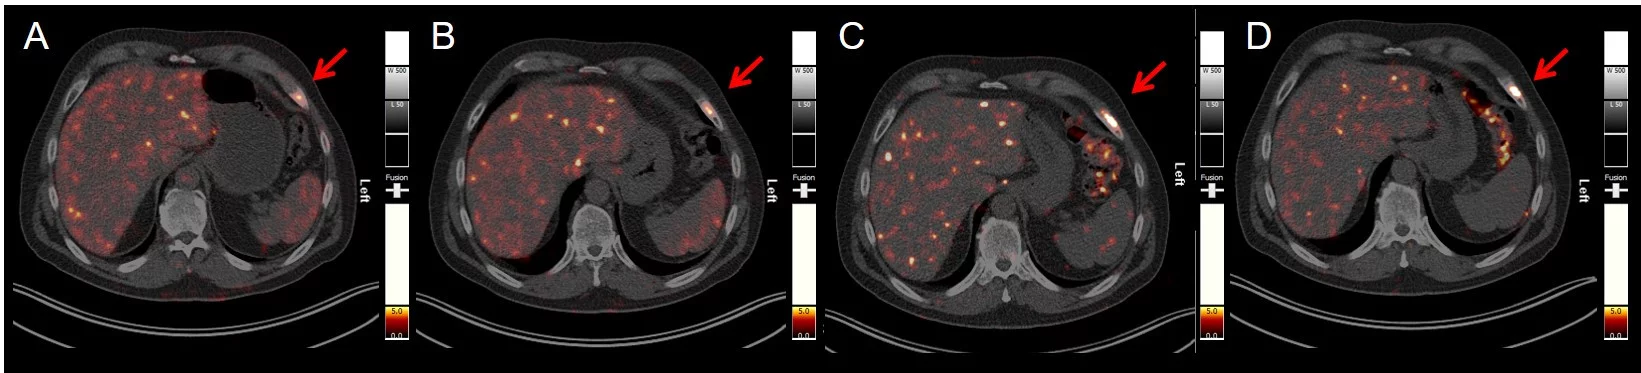

The application of 152Tb-PSMA-617 for imaging of prostate-specific membrane antigen (PSMA)-positive prostate cancer, was demonstrated in a patient with metastatic castration-resistant prostate cancer (mCRPC) at Zentralklinik, Bad Berka, Germany.

PET/CT scans (transversal slices through the upper abdomen at the level of the liver and spleen) obtained at (A) 50 min, (B) 2 h, (C) 18.5 h, and (D) 25 h, respectively after injection of 140 MBq 152Tb-PSMA-617, clearly demonstrating a PSMA-avid bone metastasis in the ventrolateral part of the left 7th rib (red arrow) with maximum uptake at 18.5 and 25 h p.i. (Figure reproduced from Müller et al. EJNMMI Research 2019, 9, 68; This is an open access article distributed under the terms of the Creative Commons CC BY license, which permits unrestricted use, distribution, and reproduction in any medium; Springer Nature).